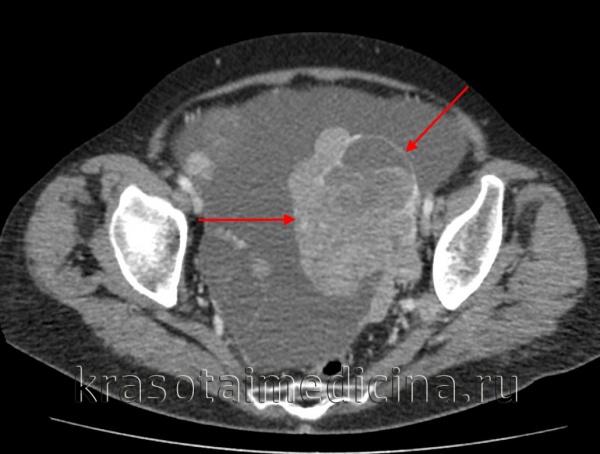

Диагноз опухолей яичников основывается на выявлении различной величины и формы опухолевого образования в малом тазу, безболезненного, умеренно или ограниченно смещаемого, с бугристой или гладкой поверхностью, имеющего плотную или тугоэластическую консистенцию. Бессимптомное развитие опухолевого процесса в яичниках на ранних стадиях заболевания вынуждает клиницистов разрабатывать более совершенные методы их распознавания и выделять так называемую группу больных повышенного риска. Степень выраженности боли зависит от индивидуальных особенностей женщины, порога ее болевой чувствительности и возможных дегенеративных изменений в опухоли. Активное раннее выявление рака яичников может быть осуществлено на основании анамнеза и данных обычного гинекологического исследования. Консистенция злокачественных опухолей яичников по пальпаторным данным неоднородная, кистозная с участками солидизации, поверхность бугристая. При попытке сместить опухоль ощущается болезненность. Подвижность опухолей часто ограничена из-за спаянности их со смежными органами. В поздних стадиях заболевания пальпируется увеличенный в размере и инфильтрированный большой сальник, обнаруживаются метастазы в пупке, надключичной области, по брюшине заднего маточно-прямокишечного углубления. Диагностика рака яичников, как и злокачественных опухолей других органов, основывается на совокупности данных анамнеза, пальпаторного обследования и результатов различных дополнительных методов. При подозрении на опухоль яичников следует обязательно проводить ультразвуковую томографию, которая является вторым этапом исследования после гинекологического. Эхоскопические аппараты, имеющие влагалищные датчики, позволяют с высокой степенью точности определить форму, размеры, локализацию опухолей и опухолевидных образований малого таза, а также составить представление об их структуре. Заподозрить рак яичников можно по беспорядочным эхо-сигналам, а также наличию множества эхонегативных теней округлой формы. Выявляется с помощью ультразвука и асцит до 1 литра. С помощью компьютерной томографии нередко удается определить локализацию и размеры опухолевого образования, а иногда оценить его внутреннюю структуру.

Чтобы избежать грубых ошибок в выборе тактики лечения больных с малосмещаемыми опухолями в малом тазу, следует помнить о необходимости исключить у них неорганную забрюшинную опухоль. Неорганные опухоли типа липом, расположенные забрюшинно, даже при небольших размерах могут симулировать опухоли яичников. В их распознавании неоценимо значение компьютерной томографии, которая позволяет не только установить забрюшинное расположение опухоли и локализовать место ее расположения, но и уточнить протяженность, связь со смежными анатомическими структурами и показать возможность хирургического удаления такой опухоли. Среди дополнительных методов исследования обязательным является цитологическое исследование мазков из осадка асцитической и плевральной жидкости, а также смывов, полученных при пункции дугласова пространства.

- Методы визуализации. С помощью трансвагинальной эхографии (УЗИ), МРТ и КТ малого таза выявляется объемное образование неправильной формы без четкой капсулы с бугристыми контурами и неодинаковой внутренней структурой; оцениваются его размеры и степень распространенности.